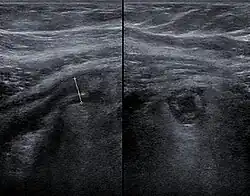

Ecografia

L'ecografia addominale, preferibilmente eseguita con tecnica doppler, è utile per diagnosticare l'appendicite, specialmente nei pazienti pediatrici. Gli ultrasuoni possono mostrare una raccolta di fluidi liberi nella fossa iliaca destra e un aumento del flusso sanguigno nell'appendice. Altri segni ecografici secondari di appendicite acuta includono la presenza di grasso mesenterico ecogeno che circonda l'appendice e l'ombra acustica di un'appendicolite.[36] In alcuni casi (circa il 5%),[37] l'ecografia della fossa iliaca non rivela alcuna anormalità nonostante la presenza di una condizione di appendicite. Questo risultato falso negativo è particolarmente frequente per i casi precoci, ovvero prima che l'appendice si distenda significativamente. Inoltre, i falsi negativi sono più comuni negli adulti, in cui quantità maggiori di grassi e gas intestinali rendono tecnicamente difficile visualizzare l'appendice. Nonostante queste limitazioni, l'imaging ecografico, utilizzato da operatori esperti, è spesso in grado di distinguere tra l'appendicite e altre malattie con sintomi simili come l'infiammazione dei linfonodi vicino all'appendice o il dolore proveniente da altri organi pelvici come le ovaie o le tube di Falloppio.